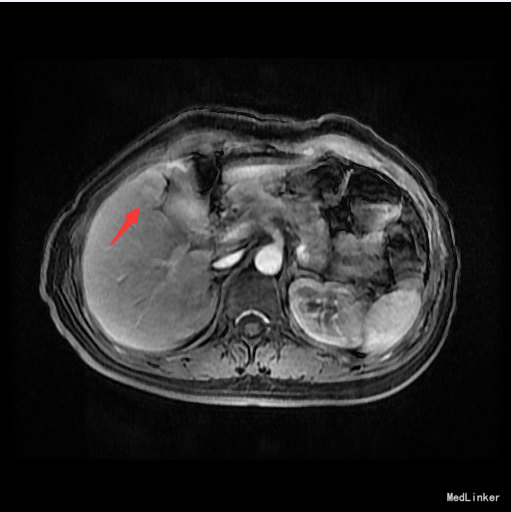

辅查:AFP 3.43ng/ml, CEA 1.47ng/ml。MR:肝S5段占位性病变(26*25mm),考虑肝癌可能性大,建议活检。

随访:术后病理示:(右肝肿物)送检肝组织部分呈结节状增生,结节间见粗细不等的纤维间隔,其内见血管增生,少量淋巴细胞及浆细胞浸润,符合肝局灶性结节状增生(FNH)。 讨论:肝局灶性结节增生(FNH)是肝内第二常见良性肿瘤,一般无临床症状,影像学表现,MRI上T1WI和T2WI与周围肝实质信号相近,增强扫描动脉期明显强化,若存在中央瘢痕,则中央瘢痕不强化,门脉期及静脉期强化程度减退,中央瘢痕则呈延迟强化。FNH需与肝癌和肝腺瘤鉴别,本例即误诊为肝癌,若存在中央瘢痕,则诊断较容易。